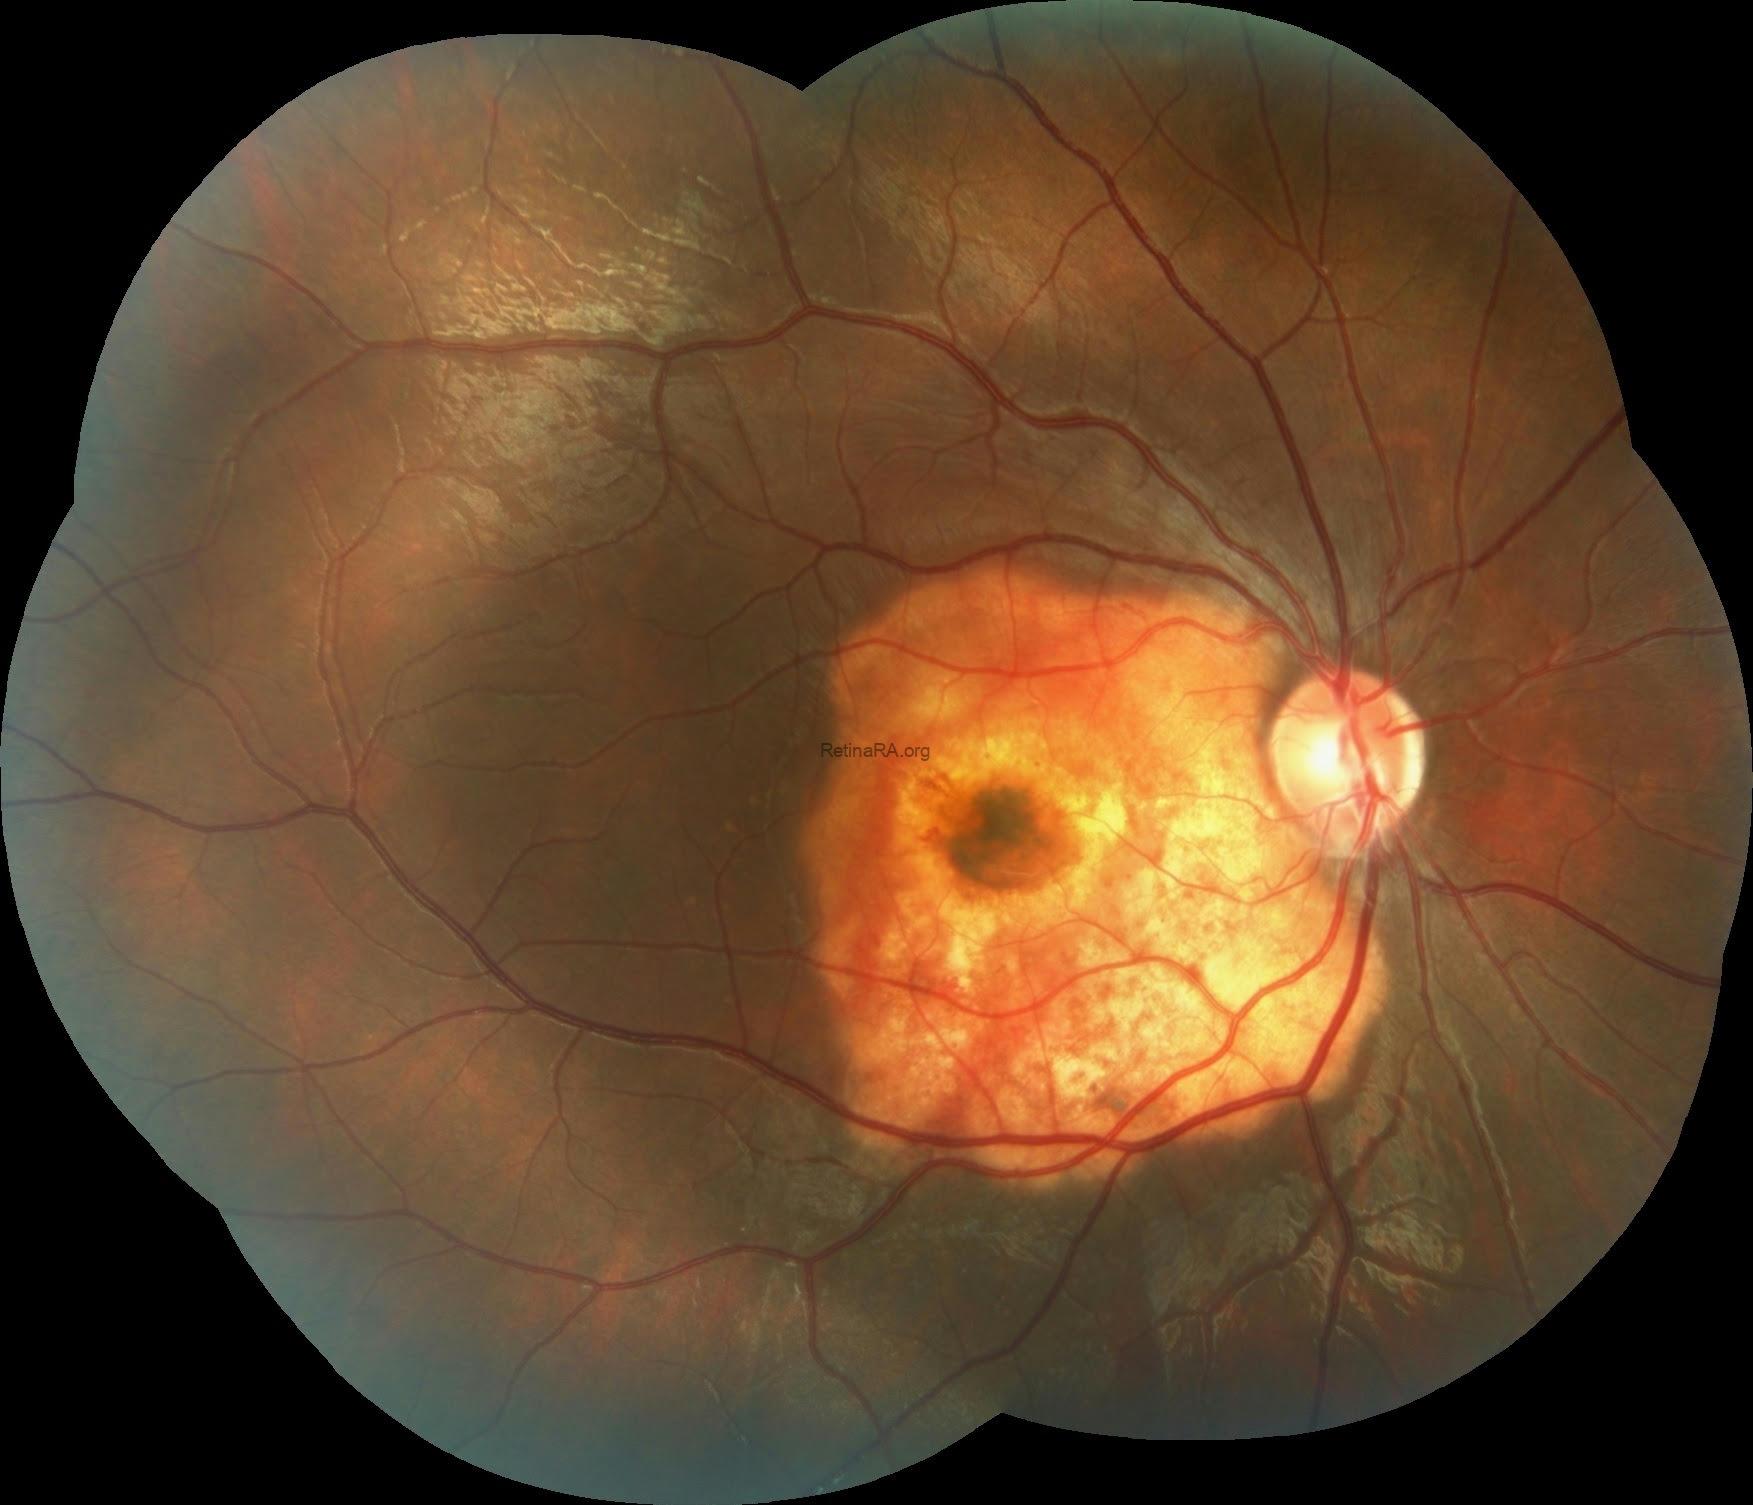

A 16-year-old male patient presented with decreased vision in his right eye. Best-corrected visual acuity was 0.1 in the right eye and 1.0 in the left eye. Anterior segment examination was unremarkable in both eyes. Intraocular pressures were within normal range bilaterally.

Fundus examination of the right eye revealed a well-circumscribed, elevated, yellow-orange lesion centered in the peripapillary and macular region in addition to foveal hemorrage while the left eye was completely normal. The lesion in the right eye has a geographic shape with irregular, scalloped borders and heterogeneous pigmentation. Central decalcification is suggested by the darker, atrophic area in the middle, while surrounding calcified regions exhibit a more solid, brighter orange tone. Retinal vessels are draped over the lesion without displacement, further supporting its subretinal/choroidal origin.